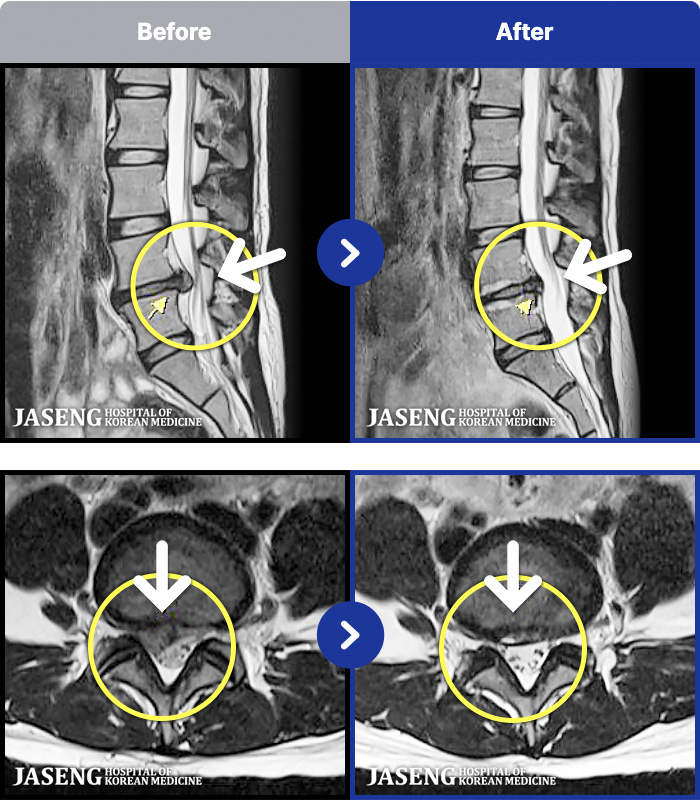

94 MRI ũ ʸ Ȯϼ.